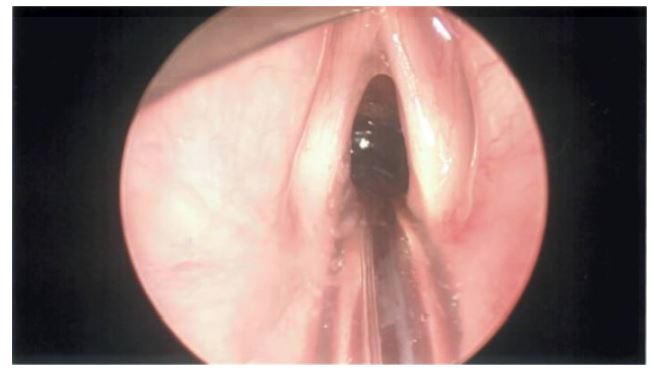

In November 2023, the patient underwent orotracheal intubation and endoscopic excision of the mass via microlaryngoscopy under general anaesthesia with a stepwise approach (see Figures 2A, 2C & 2D).The true and false vocal cords were fully visualised and seen to be healthy (see Figure 2B).The fatty mass was nearly completely resected using a cold steel technique assisted by endoscopy. Minimal bleeding was observed during the operation and no postoperative complications occurred.